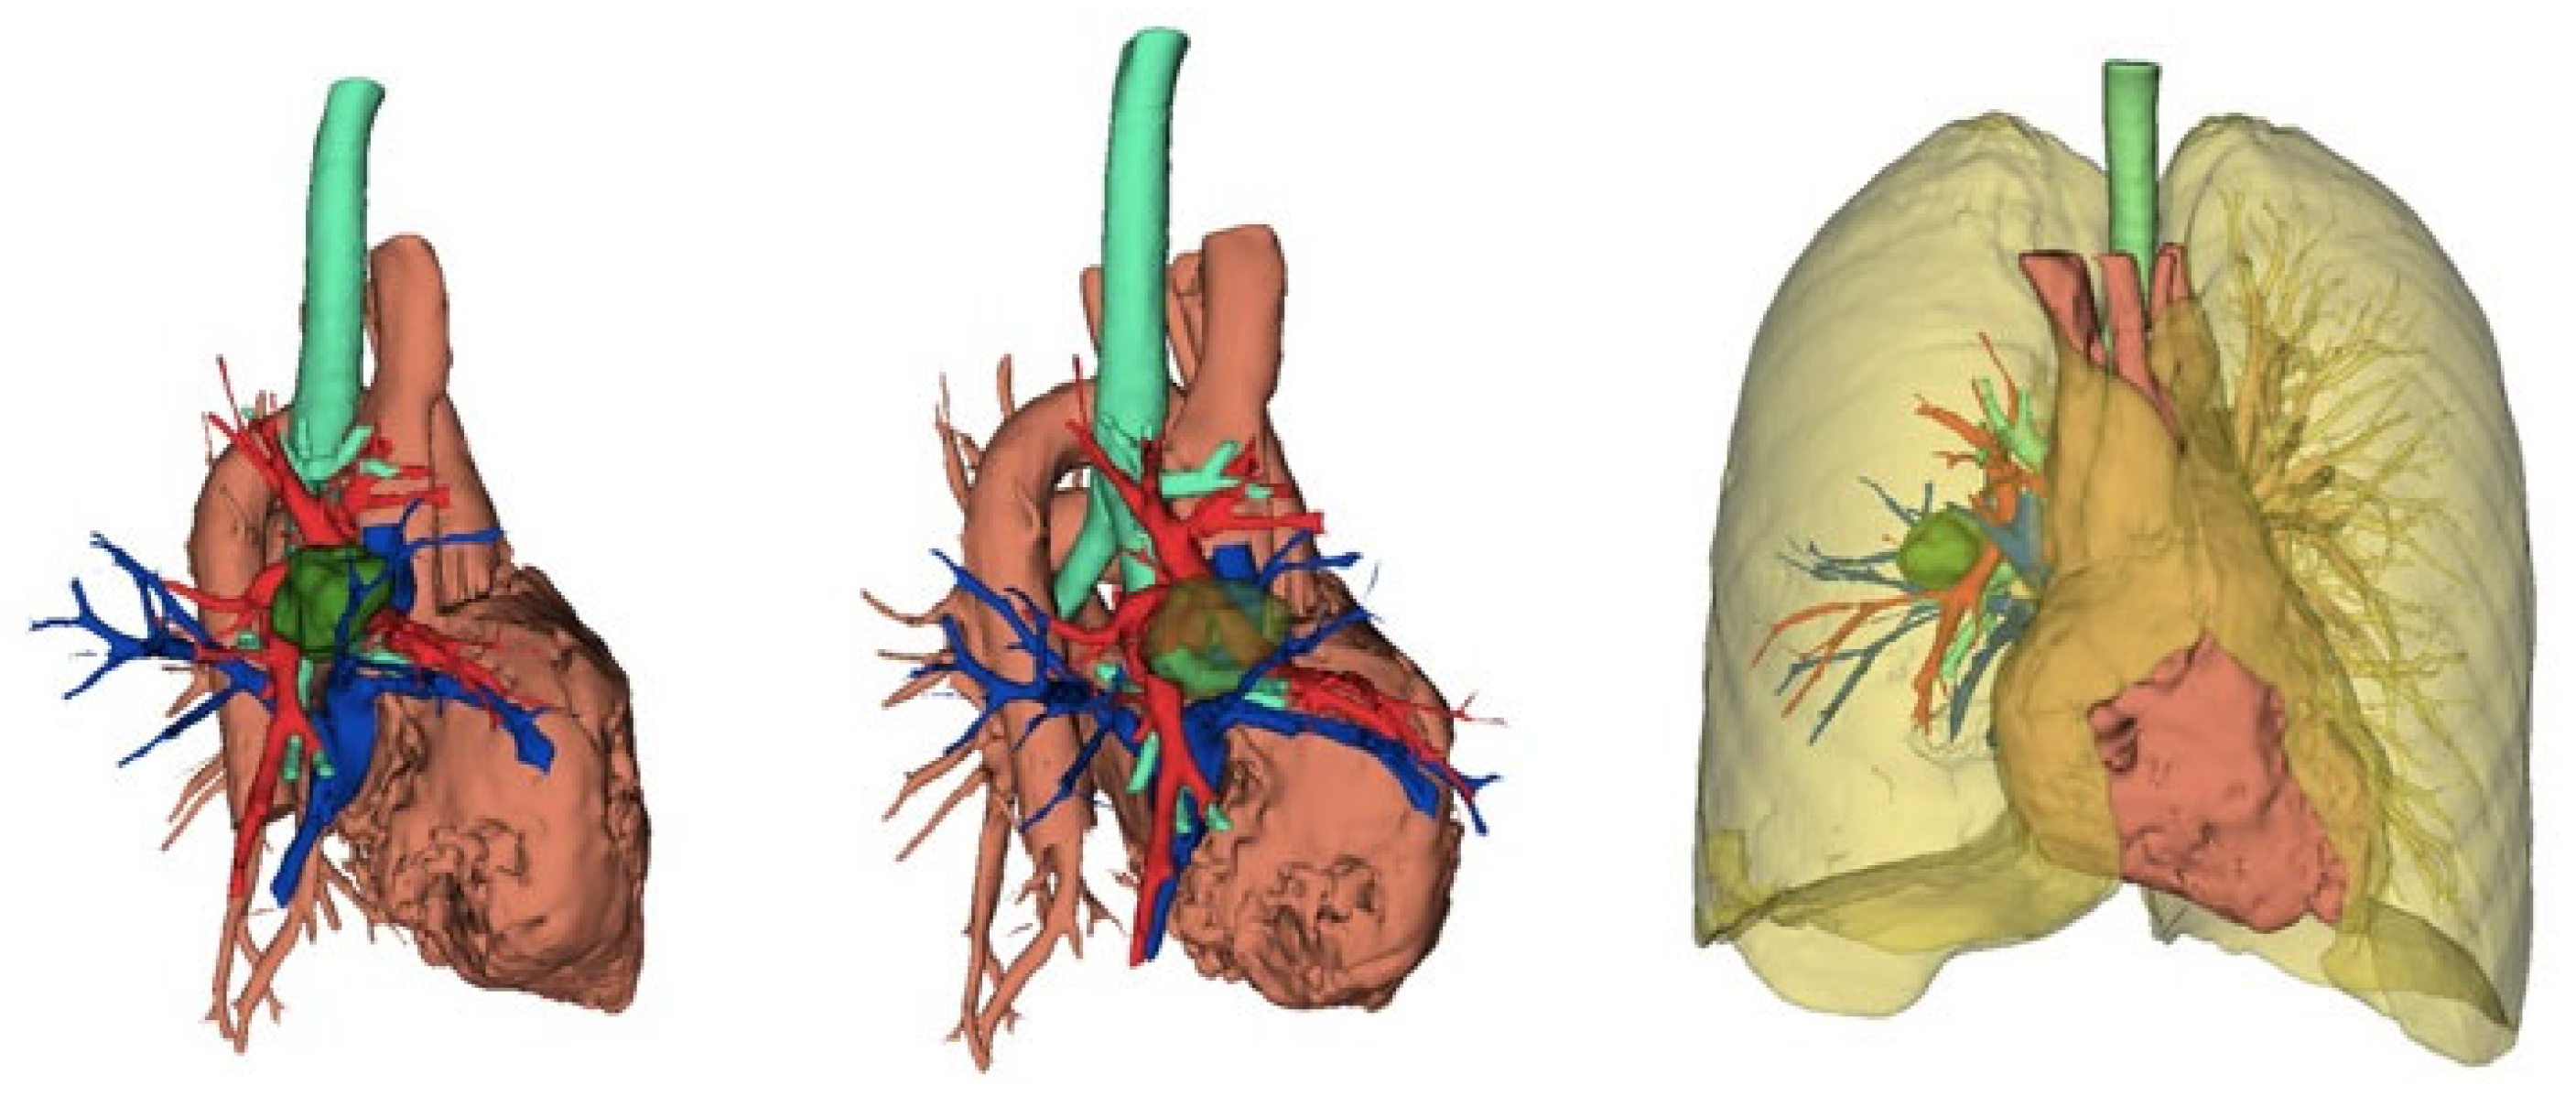

- Ikeda, N.; Yoshimura, A.; Hagiwara, M.; Akata, S.; Saji, H. Three dimensional computed tomography lung modeling is useful in simulation and navigation of lung cancer surgery. Ann. Thorac. Cardiovasc. Surg. 2013, 19, 1–5. [Google Scholar] [CrossRef] [PubMed]

- Chen-Yoshikawa, T.F.; Date, H. Update on three-dimensional image reconstruction for preoperative simulation in thoracic surgery. J. Thorac. Dis. 2016, 8 (Suppl. S3), S295–S301. [Google Scholar] [CrossRef]